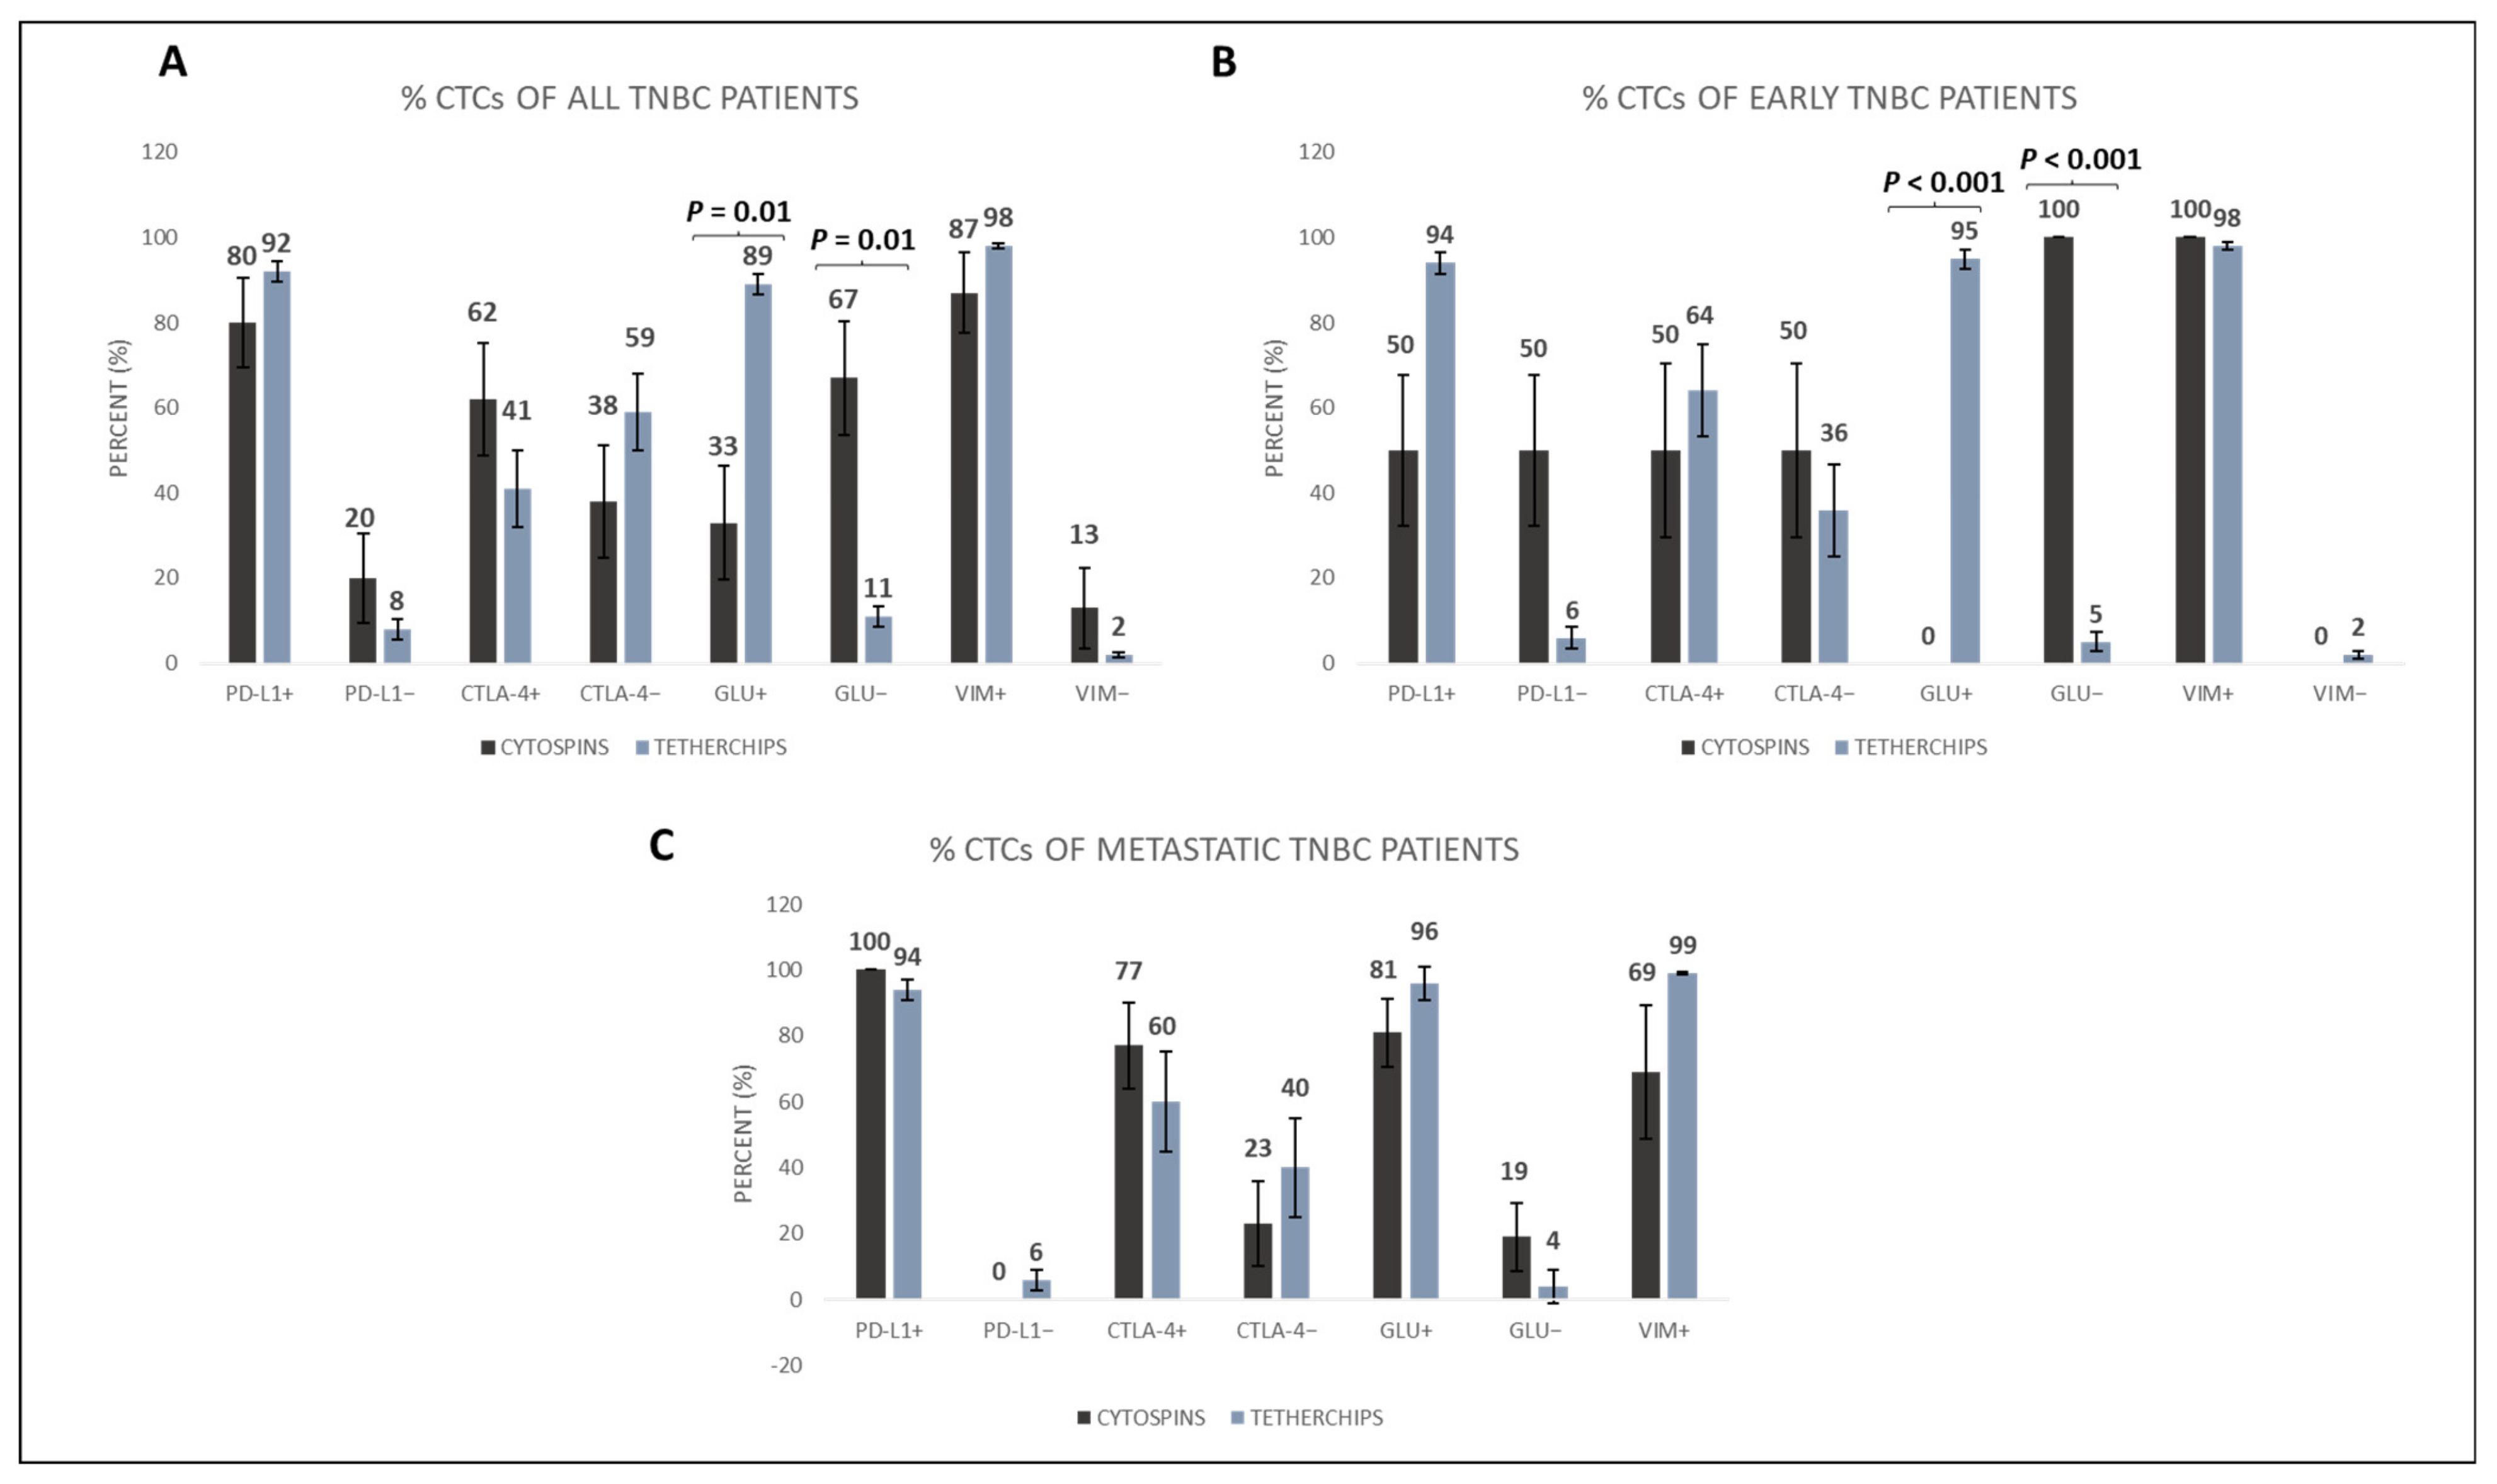

3.2. Cytospin vs. TetherChip Analysis of TNBC Patients’ CTCs

3.3. Characterization of CTCs in Cytospins and in TetherChips